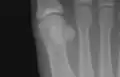

![]() The first metatarsal. (Left.) | |

Sesamoid bones at the distal end of the first metatarsal.- First metatarsal bone. Deep dissection.